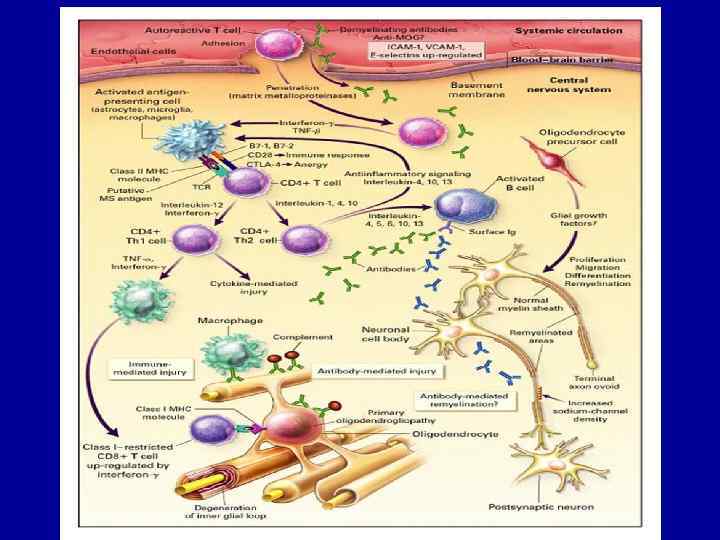

ПРЕДСТАВЛЕНИЯ О ПАТОГЕНЕЗЕ ЗАБОЛЕВАНИЯ • Под влиянием вирусной инфекции или других факторов происходит активация Т-лимфоцитов крови, которые затем проникают через гематоэнцефалический барьер (ГЭБ) и взаимодействуют с клетками ЦНС, активизируя периваскулярные моноциты и микроглию, эндотелиальные клетки и астроциты. В результате этого взаимодействия выделяются провоспалительные цитокины, гаммаинтерферон, лимфотоксин и фактор некроза опухоли альфа. Возрастающая концентрация воспалительных медиаторов ведет к нарушению ГЭБ. Нарастает интенсивность клеточных аутоиммунных реакций на антигены миелина, воспаление и демиелинизация. • Одновременно в очагах PC происходят процессы ремиелинизации (восстановление миелина), однако в большинстве случаев малоэффективные. Причина прекращения воспалительной реакции в очагах PC неизвестна. Вероятно, в этот период увеличивается концентрация противовоспалительных цитокинов: астроциты продуцируют факторы, замедляющие пролиферацию Тклеток или происходит локальная элиминация аутореактивных Тклеток путем апоптоза (запрограммированной смерти).

Figure 1. The paradigm for the role of B-cells in MS • Taken from Meinl E et al. B lineage cells in the inflammatory central nervous system environment: migration, maintenance, local antibody production, and therapeutic modulation. Ann Neurol 2006; 59: 880 -892. Reproduced with permission from John Wiley & Sons Ltd.

B-cells are directly linked to the pathogenesis of MS • B-cells are directly linked to the pathogenesis of • • MS Plasma cells and B-cells are commonly found in B-cell lesions 19 -21 and in all phenotypes of MS 22 More recently, B-cell follicles have been identified in the brain meninges of patients with secondary-progressive MS, linked to cortical lesion formation 23, 24 B-cells have also been identified in the CSF of patients with MS 25, 26 B-cells in CNS may be predictive of disease progression 26